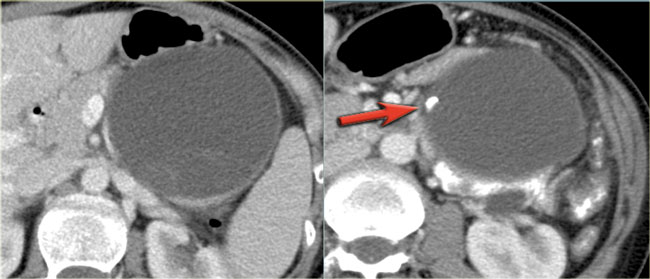

CT-images of a patient with a branch-duct IPMN who choose not to have surgery.

Over time growth of the tumor is seen with dilatation of the main duct indicating malignant transformation.

Sometimes it takes 5-8 years before a transformation is seen.

Another branch-duct IPMN found on screening with two nodules (circle and arrow).

T1W-images with fatsat before (left image) and after contrast (right image).

EUS with contrast agent revealed 2 foci without enhancement most likely mucus plugs.

6 years later the cyst was unchanged.